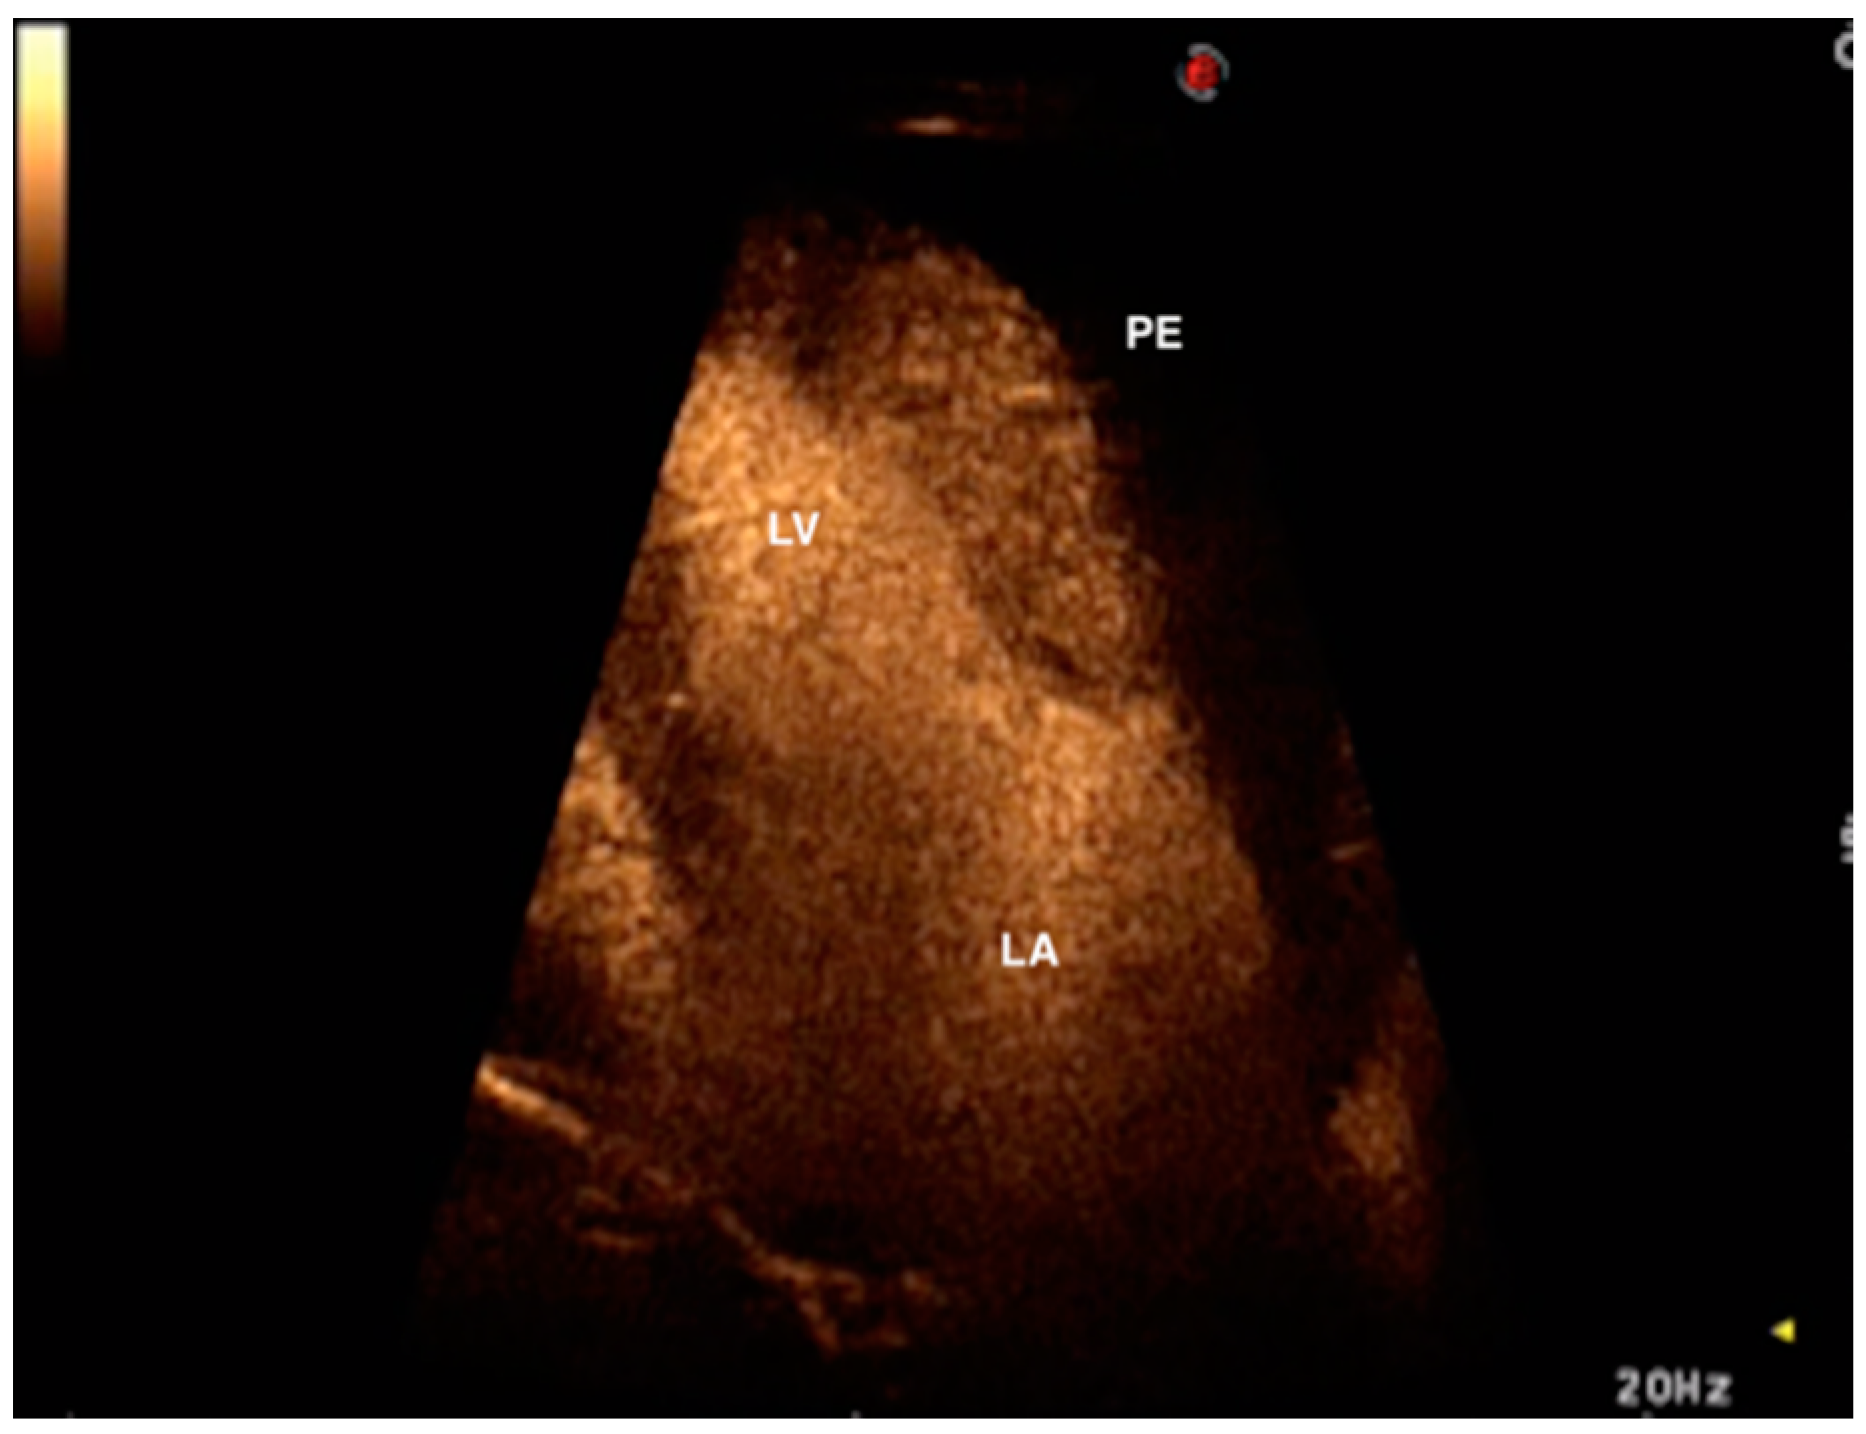

2. Case Presentation